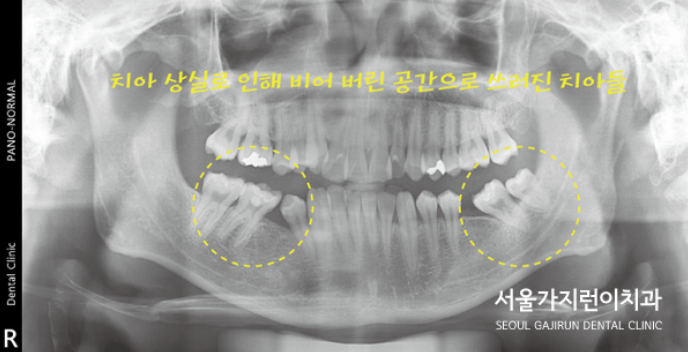

여기에 치아 상실로 비어버린 공간도 있는 케이스였는데요. 따라서 아래 하악 양쪽 치아가 쓰러져 있었는데요. 씹는 면이 기울어져 있었기 때문에 음식을 씹는 것도 쉽지 않았습니다. 이런 상태를 비수술로 치아교정을 진행해보게 되었는데요. 교정을 통해 적절한 공간을 만들어 임플란트를 식립하게 되었습니다. 환자분의 경우 MARPE 상악골 확장장치를 사용해 교정을 진행하게 되었는데요. 하악에 비해 상악골이 좁았기 때문에 위턱의 공간을 확보하면서 교정을 시작하게 되었습니다.